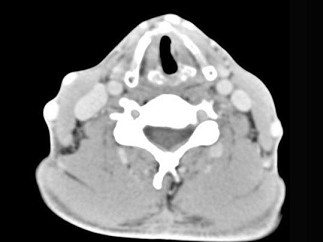

男,50岁,自觉咽喉部不适一个多月,间断刺激性咳嗽,CT扫描如图所示,正确的描述或诊断是 ( ) TJ-07321.jpg TJ-07322.jpg

• A.左侧声带内侧壁见结节状影向腔内突出,以宽基底与声带相连

• B.增强扫描结节强化不明显,密度均匀,周围结构未见受侵

• C.左侧声带息肉

• D.左侧声带乳头状瘤

• E.喉癌